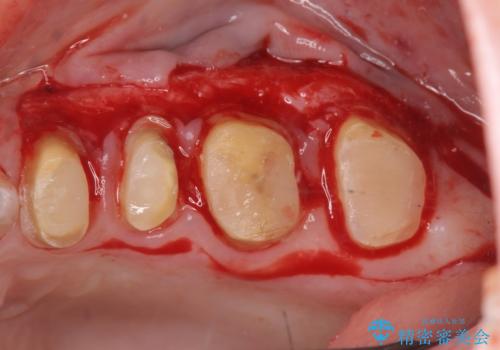

放置してしまった深い虫歯の治療

- 虫歯治療を中断し放置、痛みが出てきたため当院を初診来院されました。

虫歯の深化により根管治療、歯周外科手術を行い歯肉の状態を改善し精密なセラミッククラウンを製作する治療を計画します。

セラミック治療の長期的な予後を見込むために、根管治療、歯周外科を行いクラウン装着前の環境を整えておくことが肝要です。